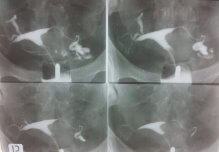

15) HSG örnekleri

İlk safha

Erken kontrol

Geç Kontrol